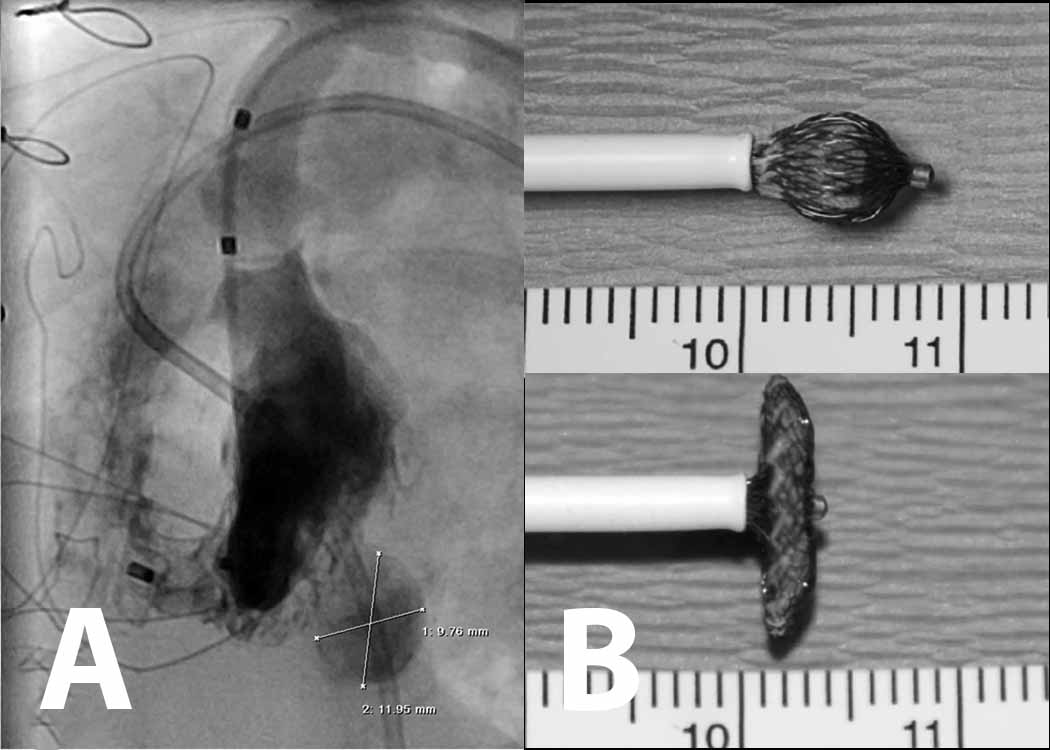

Figure 1

Figure 1 Legend: The Amplatzer® muscular Ventricular Septal Occluder Device is a radially and longitudinally symmetrical device of woven Nitinol with fabric baffles in the discs and "stuffing" in the waist. The device is attached to a microscrew (A) allowing easy retrieval for repositioning before detachment. In B the device has been implanted in a midmuscular defect.